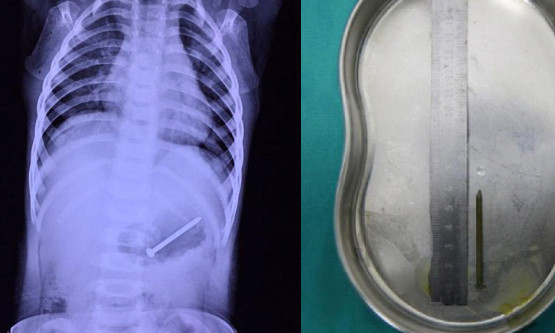

Chiếc đinh bị bé trai nuốt.

TPO - Bác sĩ đã tìm thấy chiếc đinh dài 5 cm mắc kẹt trong dạ dày bé trai một tuổi sau khi cậu bé được bà đưa tới bệnh viện chụp X-quang.

Kết quả chụp X-quang không ngoài dự đoán của người bà. Các bác sĩ phát hiện dị vật bên trong dạ dày bệnh nhi.

Cũng vì điều đó, việc chữa trị của cậu bé bị chậm trễ mất một ngày. Theo phim chụp X-quang mới nhất, chiếc đinh di chuyển khỏi vị trí ban đầu và nằm quá sâu để sử dụng phương pháp nội soi đơn giản, mà phải phẫu thuật.

Sau một giờ trong phòng mổ, ekip lấy ra thành công chiếc đinh ra khỏi dạ dày bệnh nhi. Bác sĩ phụ trách cho biết, may mắn chiếc đinh không đâm thủng dạ dày hay ruột.